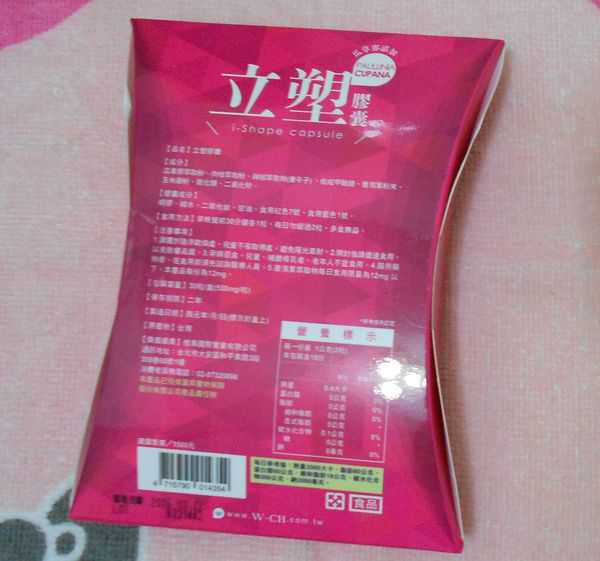

同時,謝謝【女人知己試用大隊】提供的–Supercut塑魔纖立塑膠囊

好啦,廢話不多說,就來試試繽紛小桃紅--Supercut塑魔纖立塑膠囊

每一盒Supercut塑魔纖立塑膠囊都有三小包,每一小包有10顆膠囊

Supercut塑魔纖立塑膠囊的成分有:瓜拿那萃取粉、肉桂萃取粉、辣椒萃取物(唐辛子)、吡啶甲酸鉻、番瀉葉粉末、玉米澱粉、氧化鎂、二氧化矽。

包裝是桃紅色的